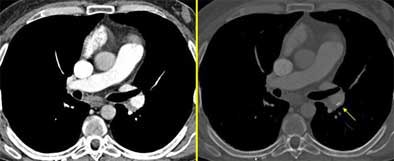

The presence of dilated arteries is another sign of chronic PE. Acute PE is seen only rarely in combination with dilatation, but more commonly in chronic PE. Thus, patients with a higher relative percentage of dilated arteries are likelier to have chronic PE.

"Additional arteries around the thorax can also develop as a consequence of this chronic obstruction of the pulmonary circulation," she said. "Here is an example of this dilatation of the internal mammary artery, and here the dilatation of the inferior phrenic artery, also participating in this collateral supply. When we have a patient with pulmonary hypertension, and when we don't know the exact etiology of this hypertension, it's interesting to have a look at these arteries."

Transverse sections are often sufficient to find the four key signs of chronic PE and render the diagnosis, but additional reformations are often needed in clinical practice, to better delineate the morphology, she said.

Pointing to another slide, Rémy-Jardin said that one patient had pulmonary hypertension, but lacked any of the key signs of chronic PE, except in a very small region characterized by low attenuation.

"Is it endo- or perivascular? We can answer the question by means of these oblique coronal reformations, where you can see this endoluminal filling defect extending up into the right upper lobar pulmonary arteries," she said. "Here you have a very thin filling defect located at the periphery of the pulmonary arteries -- it's easier to look at them on these images compared to transverse sections."